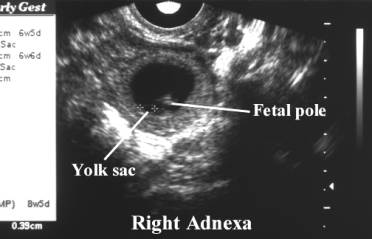

- Heterotopic gestations

describe the presence of both intrauterine and extrauterine gestations.

- Sonographic demonstration of

a normal intrauterine pregnancy is therefore not sufficient in either

symptomatic or asymptomatic patients especially after assisted

reproductive technology (ART). The adnexal and cul-de-sac should be

thoroughly assessed.

- Site of ectopic implantation

include; tubal, cornual, cervical, abdominal or ovarian.